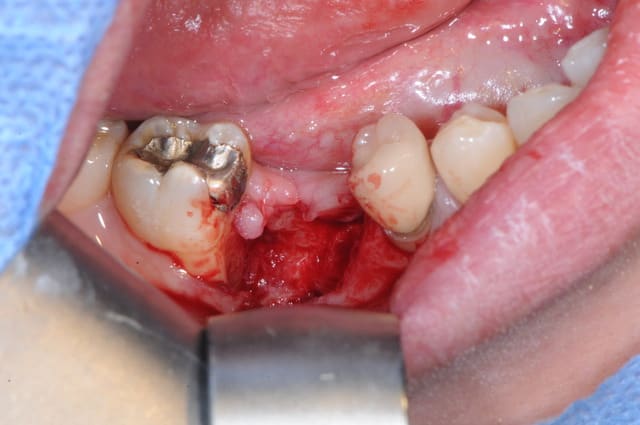

je lui ai programmé rapidement une intervention pour ce matin afin de cureter.

il a simplement fallu tirer un peu sur le séquestre